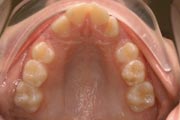

Crowding

Before